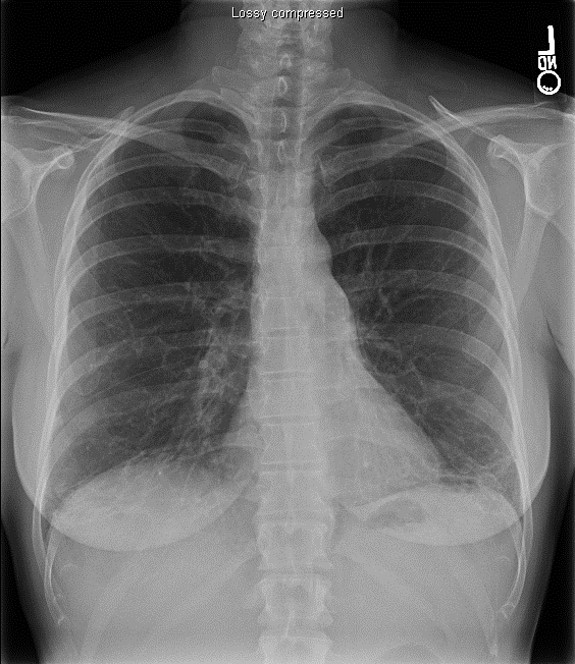

CHEST X-RAYS ARE IMPORTANT TO RULE OUT OTHER POSSIBLE CAUSES OF SHORTNESS OF BREATH

- Chest X-rays cannot solely diagnose most ILDs, but they can help rule out other causes of dyspnea, including heart disease, pneumonia, collapsed lung, emphysema, and lung cancer3,26

- When possible, previous chest X-rays should be included in the evaluation to determine whether the disease process is acute or chronic2

If an X-ray report states ILD, interstitial findings, or reticulation, the patient should be referred to a pulmonologist for an HRCT scan and further workup.2

PATIENTS WITH DYSPNEA AND/OR COUGH SHOULD HAVE AN HRCT TO LOOK FOR SIGNS OF ILD BECAUSE CHEST X-RAYS MAY APPEAR NORMAL30

Chest X-Ray

HRCT

Images courtesy of and used with permission from the American Thoracic Society.